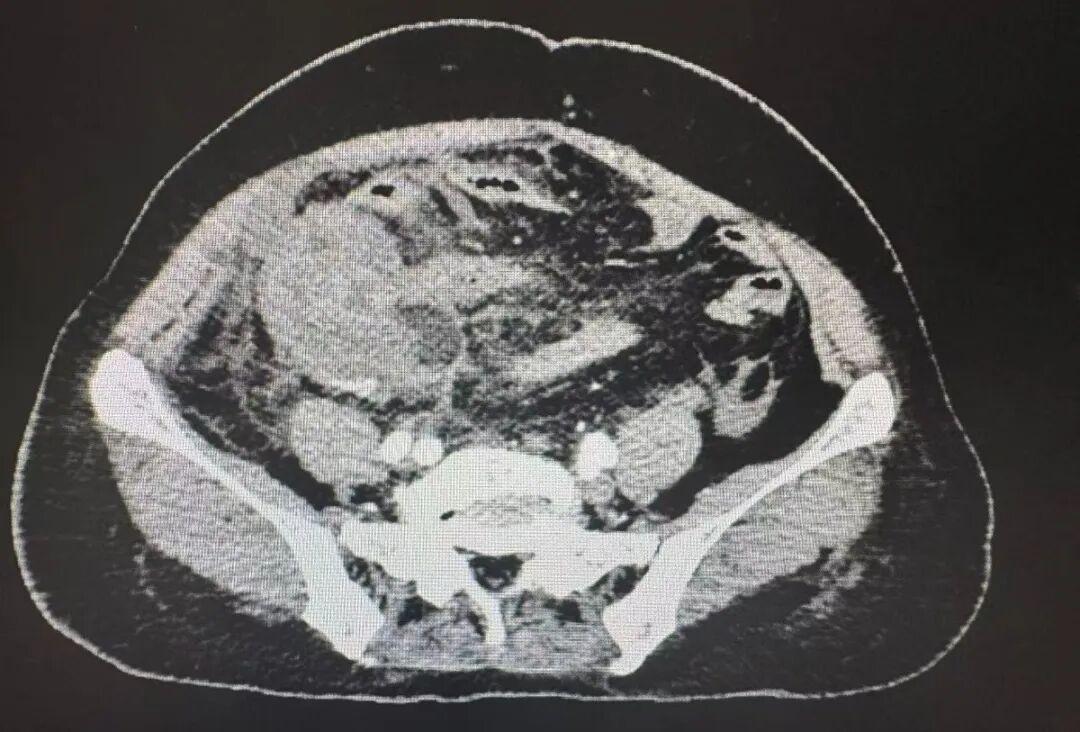

急诊检查结果显示,白细胞数值是正常值的近四倍,CT示右下腹一团糟,阑尾不仅化脓穿孔,还形成了一个大脓肿,脓液已经扩散到整个腹腔,医生考虑急性坏疽性阑尾炎伴穿孔,弥漫性腹膜炎,阑尾周围脓肿。

与家属充分沟通后,急诊腹腔镜微创手术火速进行。术中景象印证了术前的判断,当镜头探入腹腔,腹腔内里积了不少黄褐色脓液,肠子、子宫、大网膜等因为严重的炎症粘在一起。

普外科手术团队副主任医师宋书亚、医师杨慧斌就像在错综复杂的雷区里作业,小心翼翼地分离粘连的组织,最终在右侧腹腔的不同位置,找到了三个隐藏的脓肿,先后抽出了500毫升的脓液和坏死组织。